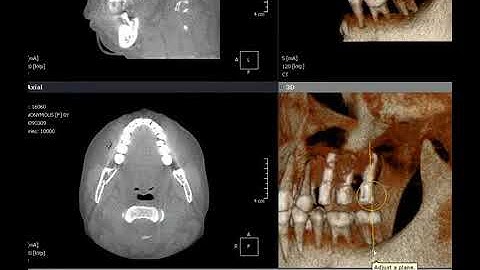

OnDemand3D Tool Tip - CPR(3D module)